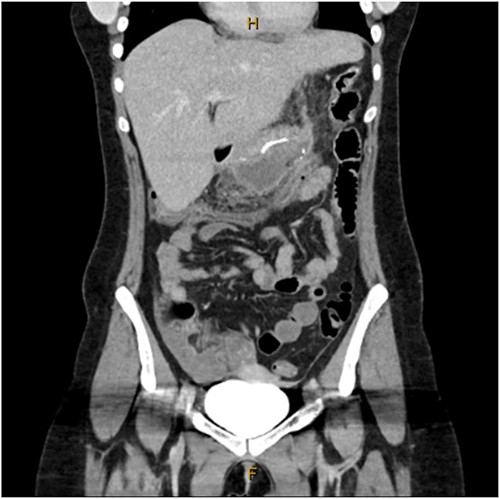

A 31-year-old female, 6 weeks post laparoscopic sleeve gastrectomy presented to the emergency department with epigastric pain and vomiting. Initial bloods showed raised inflammatory markers with a white cell count of 15.5 × 109/L and C-reactive protein of 342 mg/L. Initial CT on presentation showed the presence of a 14 × 7 × 5 cm3 gas and fluid filled collection adjacent to the staple line (Fig. 1). The patient was resuscitated with adequate fluids and kept nil by mouth. Prompt broad spectrum antibiotics were commenced. An 8Fr firm nasobiliary tube was placed directly into the collection via the defect near the GOJ under endoscopic guidance and placed on suction. During the same endoscopic procedure, a feeding nasojejunal tube was placed to ensure adequate nutrition. Given the extent of the collection, sequential advancement of the nasobiliary tube over the course of 23 days was required to ensure adequate drainage. The collection was monitored with repeat CT scans until resolution (Fig. 2). The GOJ defect was then endoscopically closed with an over the scope clip on Day 23 post presentation. The patient was discharged home post a repeat CT showing complete resolution of the collection and no oral contrast medium extending into the site of the previous collection.

Coronal CT image showing staple line collection at time of presentation. The image shows a 14 × 7 × 5 cm3 collection adjacent to the sleeve gastrectomy staple line.